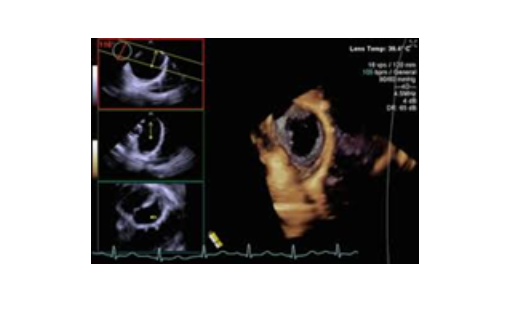

3. Siêu âm tim 3D, 4D

Khác với siêu âm 2D, khi hình ảnh thu được theo không gian 2 chiều, tức là trên 1 mặt phẳng (lát cắt), đầu dò siêu âm 3D, 4D các tinh thể áp điện theo ma trận, để thu được hình ảnh siêu âm theo không gian 3 chiều (hình khối), gọi là siêu âm 3D. Nếu có thêm chiều chuyển động (chiều thời gian) thì ta có siêu âm 4D.

Siêu âm tim 4D cung cấp hình ảnh sinh động, toàn diện, dễ hình dung hơn siêu âm 2D, đặc biệt quan trọng trong các bệnh lý sau: van động mạch chủ, van hai lá (nhất là trong kỹ thuật mitraclip: kẹp van hai lá bị hở mà không cần phẫu thuật), thông liên nhĩ, đánh giá thất trái...